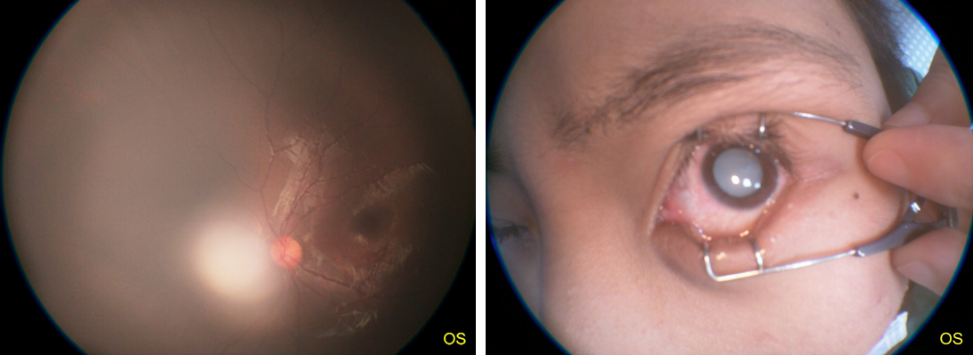

不完全性白内障(左图)和完全性白内障(右图)